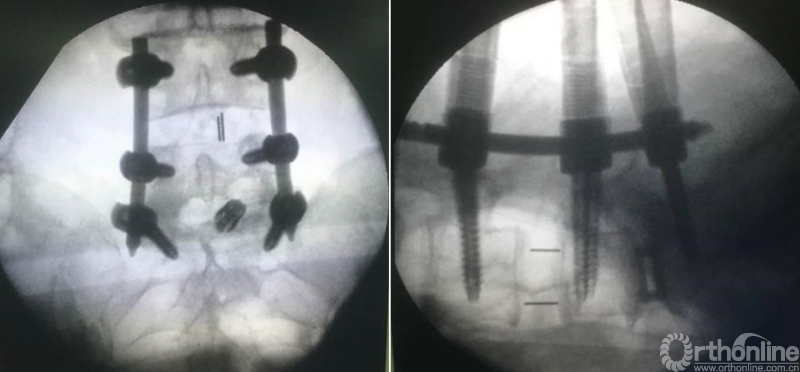

病例分享:(滑动查看)